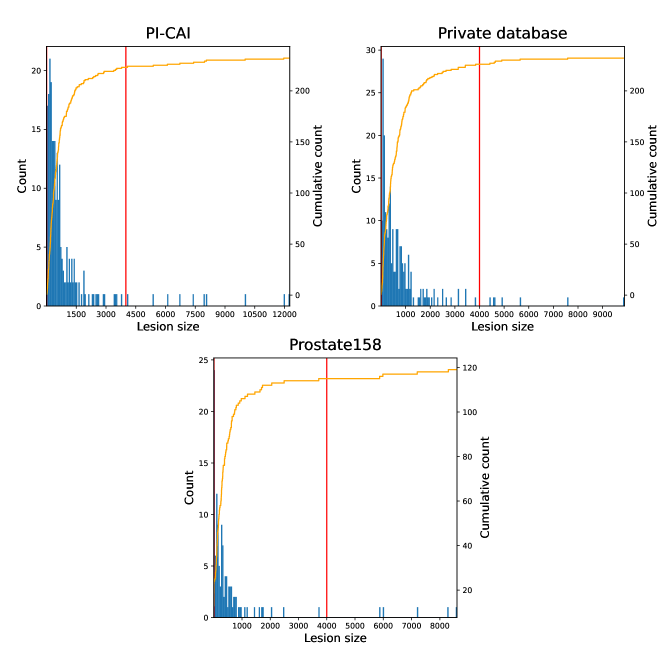

Both T2-weigthed (T2w) and apparent diffusion coefficient (ADC) MR maps were used as input channels. The latter modality was registered to the former, all images were resampled to a mm3 pixel size and cropped to volumes. Images intensities were linearly normalized into the range [0, 1] for each patient and each modality. More details about these datasets can be found on Appendices A and B, including lesion volume distributions and histograms of intensities for T2-weighted imaging and ADC maps.

Appendix A Lesion characteristics for each database

| Database | # of positive cases / total patients | # of CS lesions |

|---|---|---|

| PI-CAI | 220 / 1295 (17%) | 301 |

| Private dataset | 183 / 219 (84%) | 408 |

| Prostate158 | 82 / 139 (59%) | 236 |

Appendix B Characteristics of MRI modalities for each database